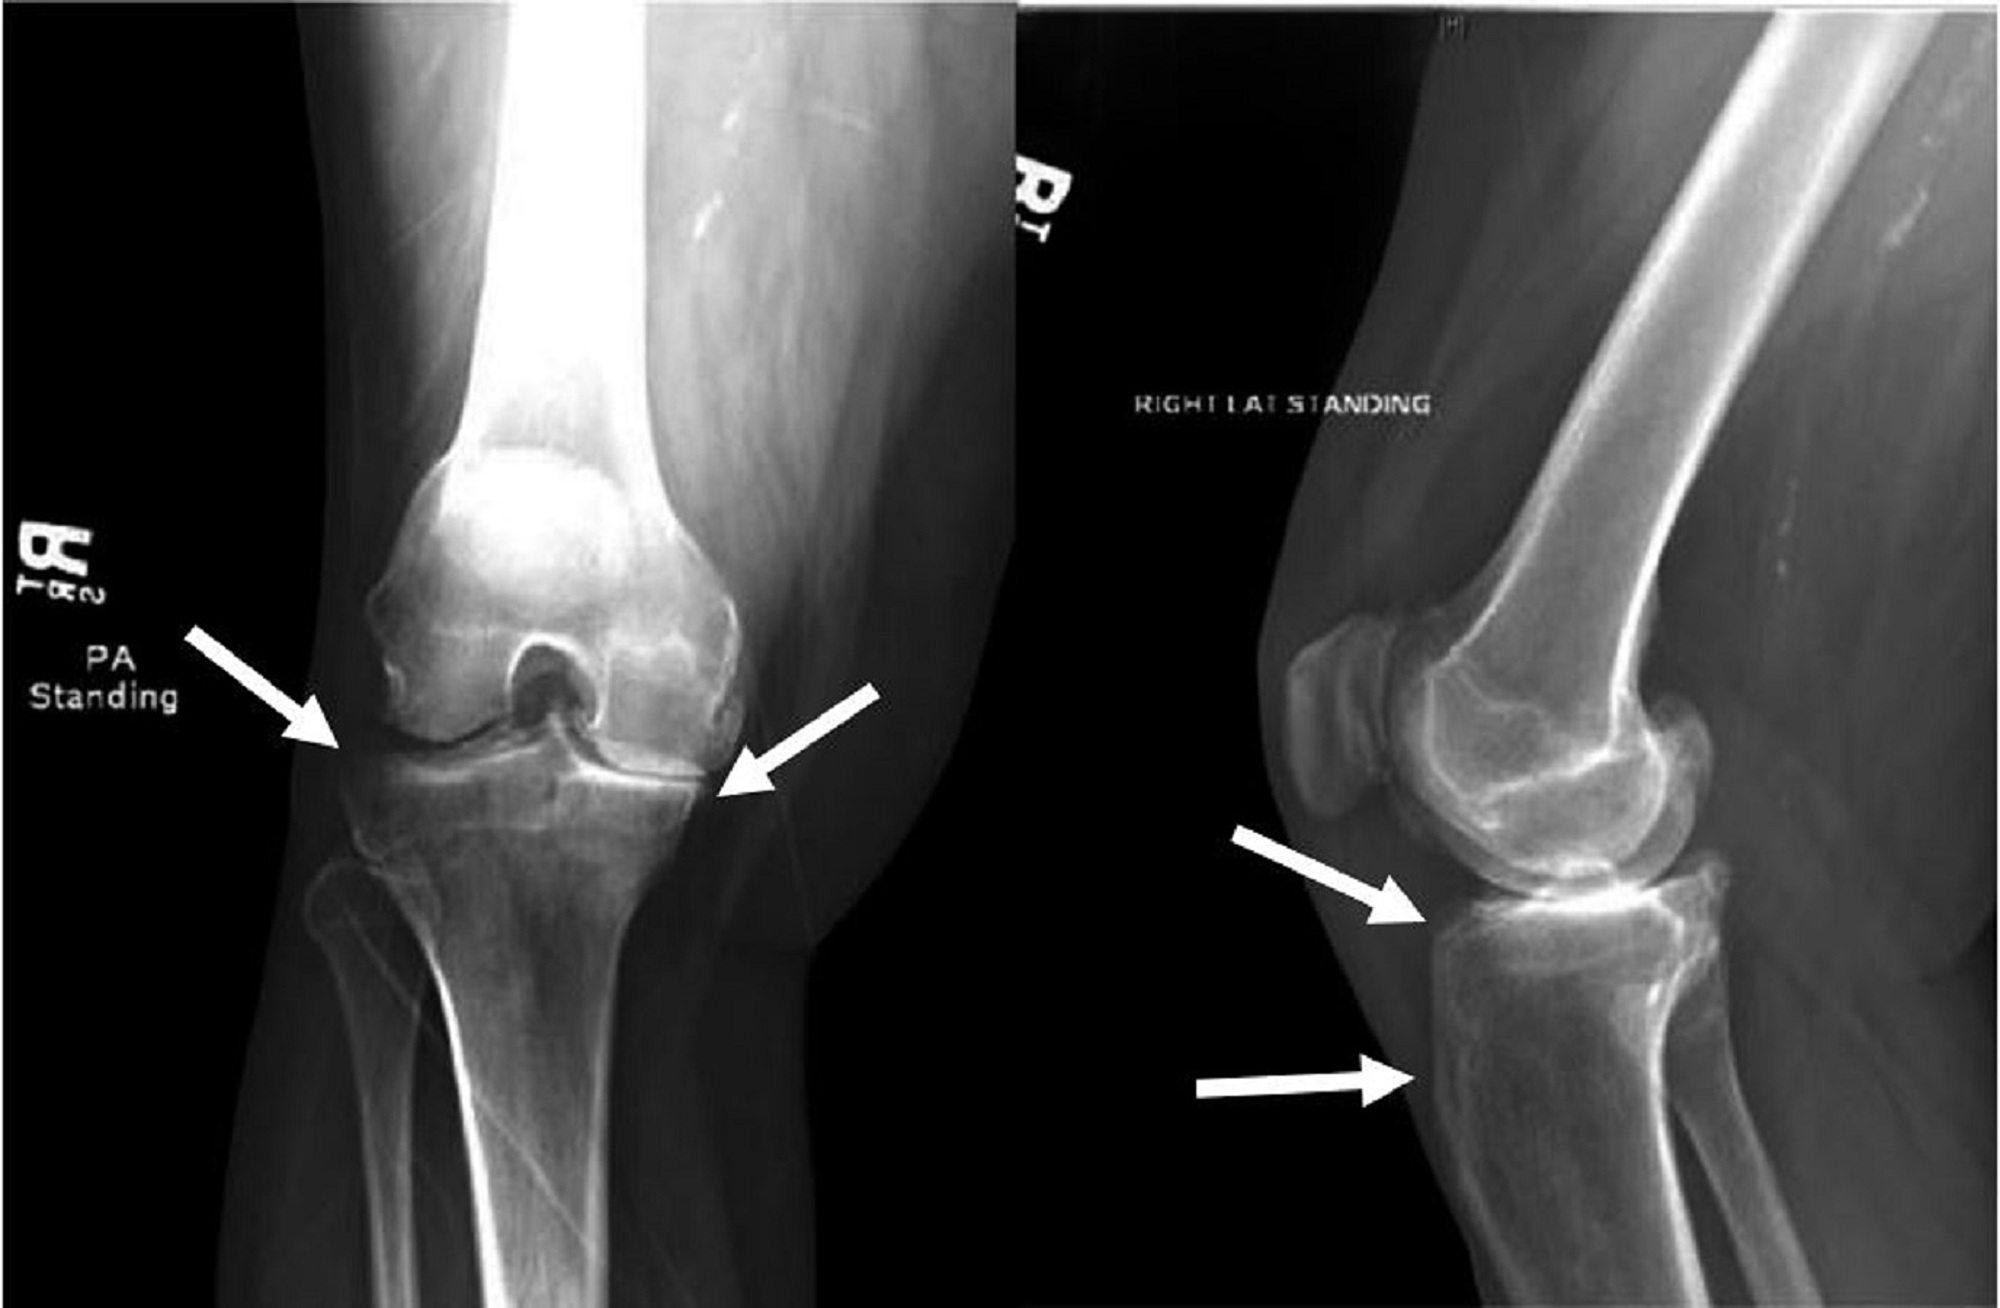

From www.mdpi.com

Medicines Free FullText Management of SalterHarris Type 1 Osteomyelitis Levofloxacin Osteomyelitis is an inflammatory condition of bone secondary to infection; The management of complex orthopedic infections usually includes a prolonged course of intravenous antibiotic agents. Symptoms of acute osteomyelitis include pain,. It may be acute or chronic. In this narrative review, we aim to provide a comprehensive overview of the existing evidence on three important aspects of systemic antimicrobial. Treatment. Osteomyelitis Levofloxacin.